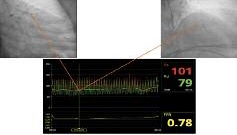

ЭКГ от 20.03.2018: ритм синусовый, ЧСС 67 уд/мин (рис. 1). Общие анализы крови и мочи, коагулограмма – без клинически значимых отклонений. В биохимическом анализе крови: общий ХС 6,93 ммоль/л, ХС ЛПНП 5,25 ммоль/л, в остальном – значения в референсных пределах. Суточное мониторирование ЭКГ: основной ритм синусовый, средняя ЧСС – 59 уд/мин, максимальная ЧСС – 117 уд/мин, минимальная ЧСС – 48 уд/мин. Эпизод депрессии сегмента ST -0,9 мм продолжительностью 6 мин, сопровождался одышкой, зарегистрирован во время физической нагрузки; 15 одиночных наджелудочковых экстрасистол. Паузы не зарегистрированы. ЭхоКГ от 22.03.2018: уплотнение стенок аорты, створок аортального клапана с развитием аортальной регургитации 1-й степени. Полости сердца не расширены, стенки не утолщены. Зон нарушения локальной сократимости миокарда ЛЖ не выявлено, глобальная сократимость миокарда ЛЖ удовлетворительная (фракция выброса 60%). Признаков легочной гипертензии не выявлено. Ультразвуковое исследование почек и почечных артерий от 22.03.2018: небольшое расширение чашечно-лоханочной системы почек. Киста правой почки. Симметричный кровоток без признаков гемодинамически значимого стенозирования. Скоростные показатели в пределах нормальных значений. Дуплексное сканирование экстракраниального отдела брахиоцефальных артерий от 27.03.2018: стеноз до 60% в устье правой наружной сонной артерии, в остальном – без гемодинамически значимого стенозирования.

Рис. 1. ЭКГ от 20.03.2018: ритм синусовый, ЧСС 67 уд/мин.